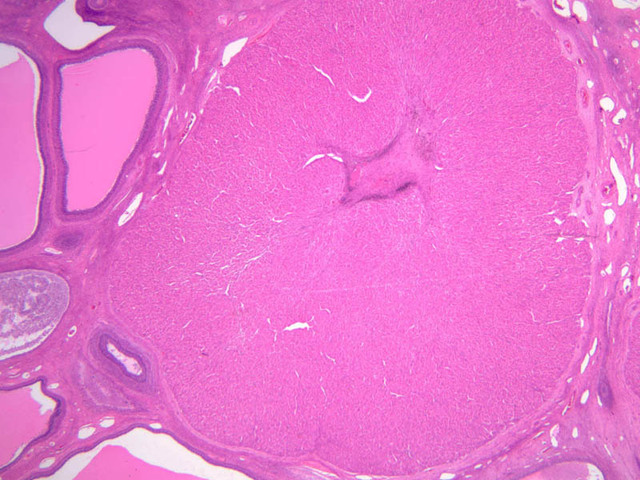

The ovary is a somewhat oval and slightly flattened organ situated near the fimbriated end of the uterine tube (B-94, monkey ovary, H&E [1x, 1x]; B-95, monkey ovary, H&E [1x-labeled, 1x]; B-96, monkey ovary and tube, H&E [1x]; B-54, H&E [1x, 1x]). Its exposed surface is covered by a mesothelial sheet of squamous or cuboidal epithelium. Just deep to this is an ill defined area of dense fibrous connective tissue referred to as the tunica albuginea (B-96 [2.5x-labeled, 10x-labeled, 20x, 40x]).

The ovary has two major regions – the cortex and the medulla. The cortex is the broad peripheral area containing follicles in various stages of development, whereas the medulla is the more central area displaying profiles of large blood vessels. These blood vessels gain entrance via the mesovarium. The division between the cortex and medulla is indistinct. In the cortex, stromal cells occupy the areas between the follicles. These cells are closely packed, fusiform (spindle shaped), and have the potential to differentiate into a specialized component of the maturing follicle (theca folliculi).